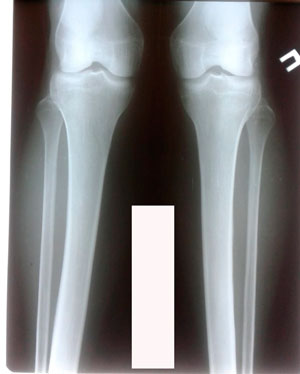

Исходник - 28 лет.

Дата операции - 03.01.2020.

перед крутками

Дата снятия аппаратов - 27.03.2020

Срок сращения - 87 дней.